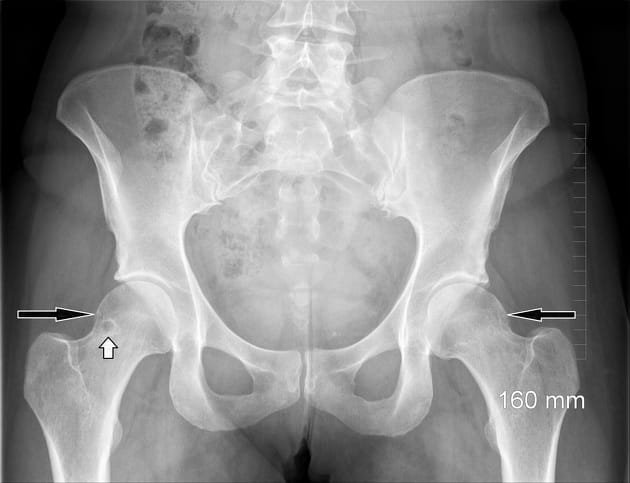

- Radiografias do quadril para identificar deformidades ósseas (CAM ou PINCER).

- Tipo CAM: Presença de uma protuberância óssea na junção cabeça-pescoço femoral, que leva a um impacto durante os movimentos de flexão e rotação interna do quadril.

- Tipo PINCER: Excesso de cobertura óssea no acetábulo, causando impacto na borda acetabular anterior.

- Tipo Misto: Combinação de deformidades CAM e PINCER, sendo a apresentação mais comum.